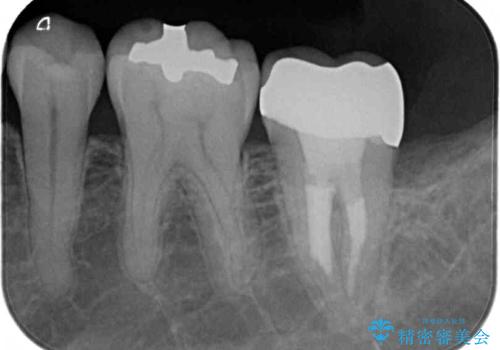

レントゲン写真より根管治療のやり直しをお勧めしたところ、ラバーダム使用下で処置を行うことを希望されたため、根管治療を行った後にオールセラミッククラウンにて補綴治療を行うこととしました。

後方は歯肉内にまで虫歯が及んでいたため、歯肉の一部を切除して、クラウンとの境目を明示して処置を行いました。